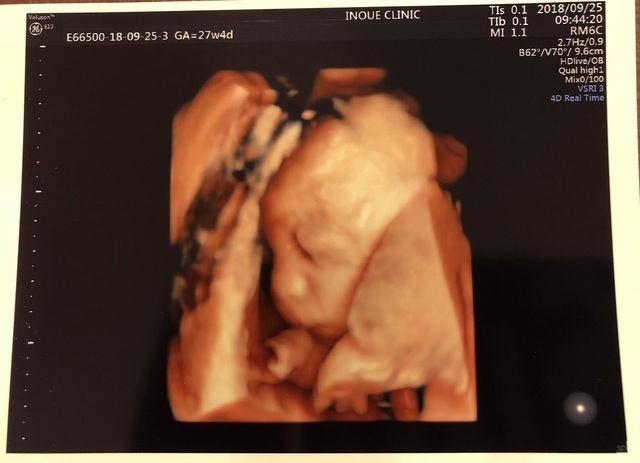

27週4日(27w4d・女の子)|べーさん831 さん(29歳)

エコー写真撮影時のエピソード:

初めての我が子は女の子!妊娠5ヶ月頃から胎動もわかるようになり、日に日に激しくなっていく胎動に驚いていました。

どんなお転婆娘がお腹にいるのかなー?なんて思っている頃に撮影したエコー写真…。「いえーい!」と言っているようなポーズ、笑顔に見えて、思わず笑ってしまいました!